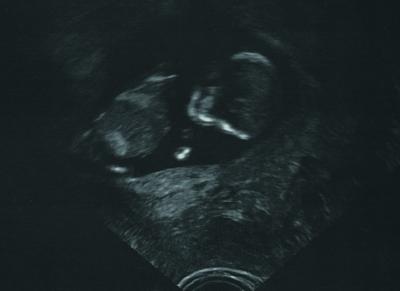

endlich kann auch ich ein schönes Bildchen ins Netz stellen - und ich bin so froh, daß alles so gut in Ordnung ist. Bin richtig stolz - ist schon ein richtiges Babykopf zu sehen....und ein dickes Bäuchlein ...